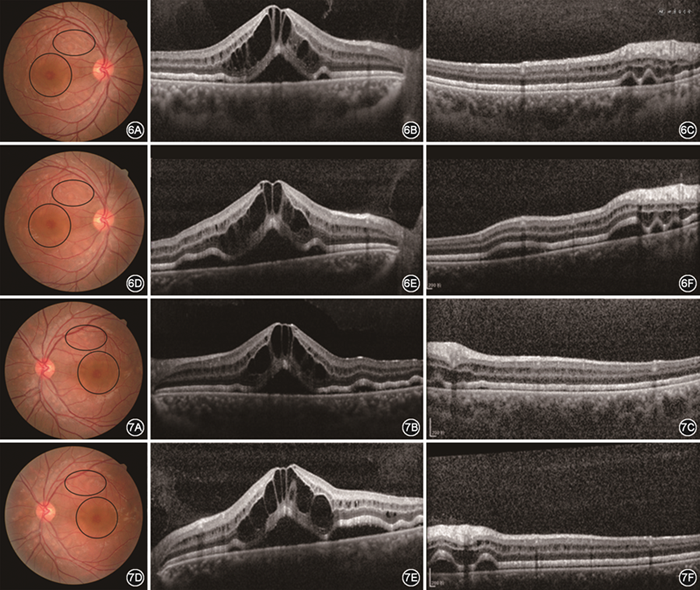

患者男性,35岁。因“自觉双眼视力下降2周”于2019年 6月5日就诊于云南大学附属医院眼科。患者无眼红、疼痛以及感冒等上呼吸道感染病史,亦无全身重大疾病史;父母非近亲结婚,家族史无特殊。眼部检查:双眼视力0.8,不能矫正。双眼眼前节未见明显异常。眼压检查正常。彩色眼底像提示双眼眼底呈现出对称性多发黄白色斑点及黄斑圆形晕环,炫彩眼底检查提示视网膜神经上皮水肿及黄白色病变区蓝绿信号增强(图1);眼底自发荧光黄斑水肿区呈花瓣样相对高荧光(图2),上、下血管弓处病变区呈现出斑点状高自发荧光(图2),其余视网膜未见明显异常自发荧光;荧光素眼底血管造影结果提示造影过程中黄斑区及黄白色病变区均未见明显荧光素渗漏,视网膜血管均未见明显异常荧光(图3);双眼荧光素脉络膜血管造影提示在早期黄斑区呈弱荧光晕,中期可见黄斑区呈椭圆形弱荧光,上下血管弓区可见多个团状、斑状弱荧光,部分中央区呈稍强荧光,晚期背景荧光及视网膜血管荧光均已排空呈弱荧光,黄斑区呈椭圆形弱荧光,上、下血管弓及视盘旁呈现出团状、斑状稍强荧光(图4);眼底相干光层析成像术(optical coherence tomography,OCT)检查结果提示双眼均呈现出黄斑区神经上皮层间多囊样积液及神经上皮层下积液,椭圆体带增厚、反射增强(图5)。全身检查:抗溶血性链球菌素O 14.1 U/ml,类风湿因子11.90 U/ml,超敏C反应蛋白0.157 mg/L,红细胞沉降率正常,乙型肝炎抗原阴性、抗体阳性,丙型肝炎抗体阴性,人类免疫缺陷病毒(human immunodeficiency virus,HIV)抗体阴性,梅毒抗体阴性,梅毒快速血浆反应素试验阴性,结核抗体阴性。结合病史、眼部多模式检查及全身检查情况诊断为急性渗出性多形性卵黄样黄斑病变(acute exudative polymorphous vitelliform maculopathy,AEPVM)。患者未给予特殊治疗,1周后复查可见眼底黄白色病灶部分有融合、扩大,黄斑区水肿情况较前加重;黄斑区OCT图像提示神经上皮层间、层下积液较前增多;黄白色病变区OCT提示椭圆体带突起明显增多,神经上皮层下积液增多(图6,7)。